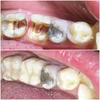

Tooth Decay